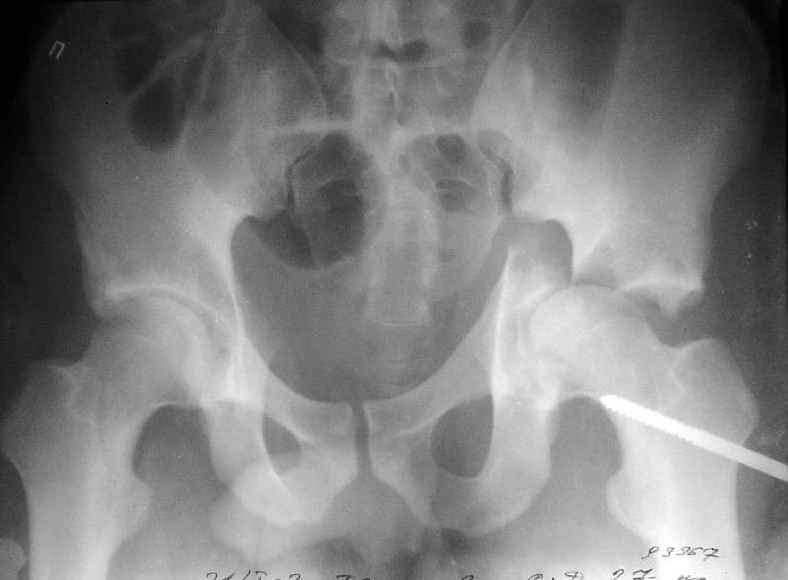

Пациент переведен в нашу клинику на 5 день после множественной травмы 25.01.2003 - двустороннее повреждение вертлужных впадин, разрыв левого крестцово-подвздошного сочленения. Вывихи обоих бедер. В месте первичного поступления подвздошный вывих правого бедра вправлен 26.01.2003, наложено вытяжение за левую вертельную область. Остеосинтез левой вертлужной впадины выполнен у нас 6.02.2003. Вопрос: надо ли синтезировать задне-верхний край правой вертлужной впадины?

правую впадину собрали здорово! Мои поздравления Рункову. Сами меня учили-учили, а где же запирательная проекция левой вертлужной

впадины. Такое впечатление что на КТ есть интерпозиция кусочком, тогда уж точно надо туда залесть, а так, я считаю не стоит.

Уважаемый Алексей, через месяц после повреждения обострять травму, чтобы продлить "колясочный" срок? Второй сустав станет опорным не скоро.Головка на Ртг концентрически вставлена, задний фрагмент не интерпонирует, лимбус,по видимому тоже, ямочный фрагмент мешать не должен,герметизирующую манжету адекватно восстановить, обычно, не удается. Выгоды от оперативного вмешательства сомнительны. Я бы оперировать не стал.Еще месяц без нагрузки (по меньшей мере) и в нашей "конторе"- МОНИКИ(Вы наверняка знаете О.Ш.Буачидзе) положились бы на ощущения пациента при активных движениях правым бедром. Можно и сейчас проверить на возможность блокады и тогда принимать окончательное решение.

Согласен, что нужна вторая проекция.

Если нагрузка на конечности будет не ранее 5-6 недель,оперировать не стоит. Считаю, что эндопротезирование справа не будет нужным.